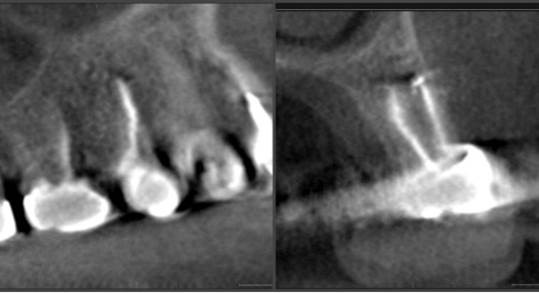

Clinical case: Digital Data Save concept in upper jaw premolar area

- Courtesy of Dr. Lysov Alexander Dmitrievich & Dr. Sofronov Matvey Vitalievich, Russia -

Keywords

AnyRidge, R2GATE, R2GATE guide, ISQ value, initial stability, immediate loading, KnifeThread, maxillary posterior, #14, Digital, Dr. Lysov Alexander Dmitrievich, Dr. Sofronov Matvey Vitalievich, zirconia abutment, CAD/CAM crown

“AnyRidge & R2GATE show stable results

after immediate extraction, immediate implant placement, & immediate loading,

even with low bone density.”